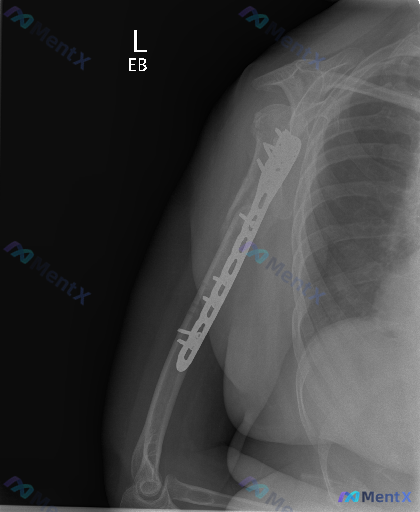

整理到一份左肱骨骨折内固定术后的正位X光片资料,大家可以一起看看: - 患者是左侧肱骨骨折术后复查,影像显示左侧肱骨近端至中段有解剖锁定钢板及多枚螺钉固定,钢板沿肱骨外侧放置,与骨皮质贴合紧密,未见明显钢板断裂、螺钉松动退出。 - 肱骨干可见陈旧性骨折痕迹,骨折线已模糊,断端周围有连续性骨痂形成;肱...